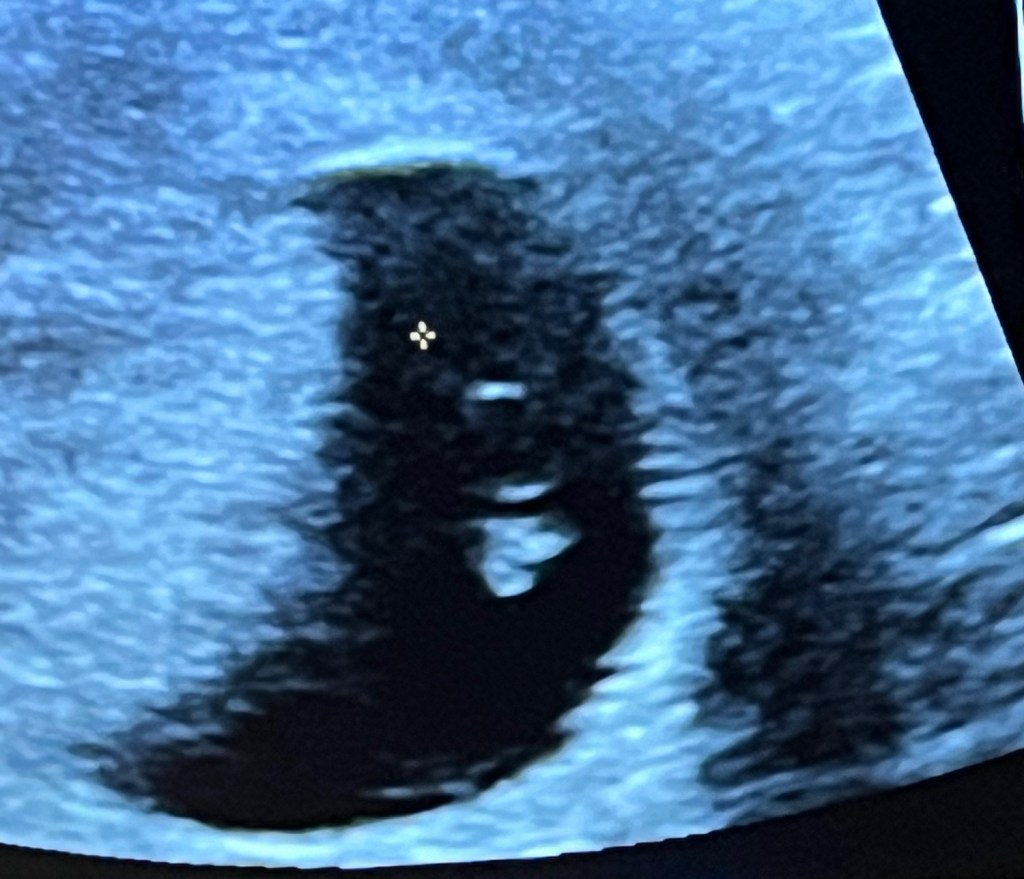

Today I am in the heartache stage. My two little lines appeared once again. I had such hopes my thoughts were this time it is going to happen. This time will be my time. I book my HCG tests both come back positive. I get my dating scan, I originally thought I was further along than I was only to be told all seems well but only measuring 6 weeks. No worries I think to myself I’ll just wait. My obstetrician booked another scan 12 days after the official. Today was that 12th day. I walk in with high hopes. I should be 8+2 measured only to be told their has been very little growth. I am still measuring at 6 weeks.

This is my scan from today – measuring the same as 12 days ago